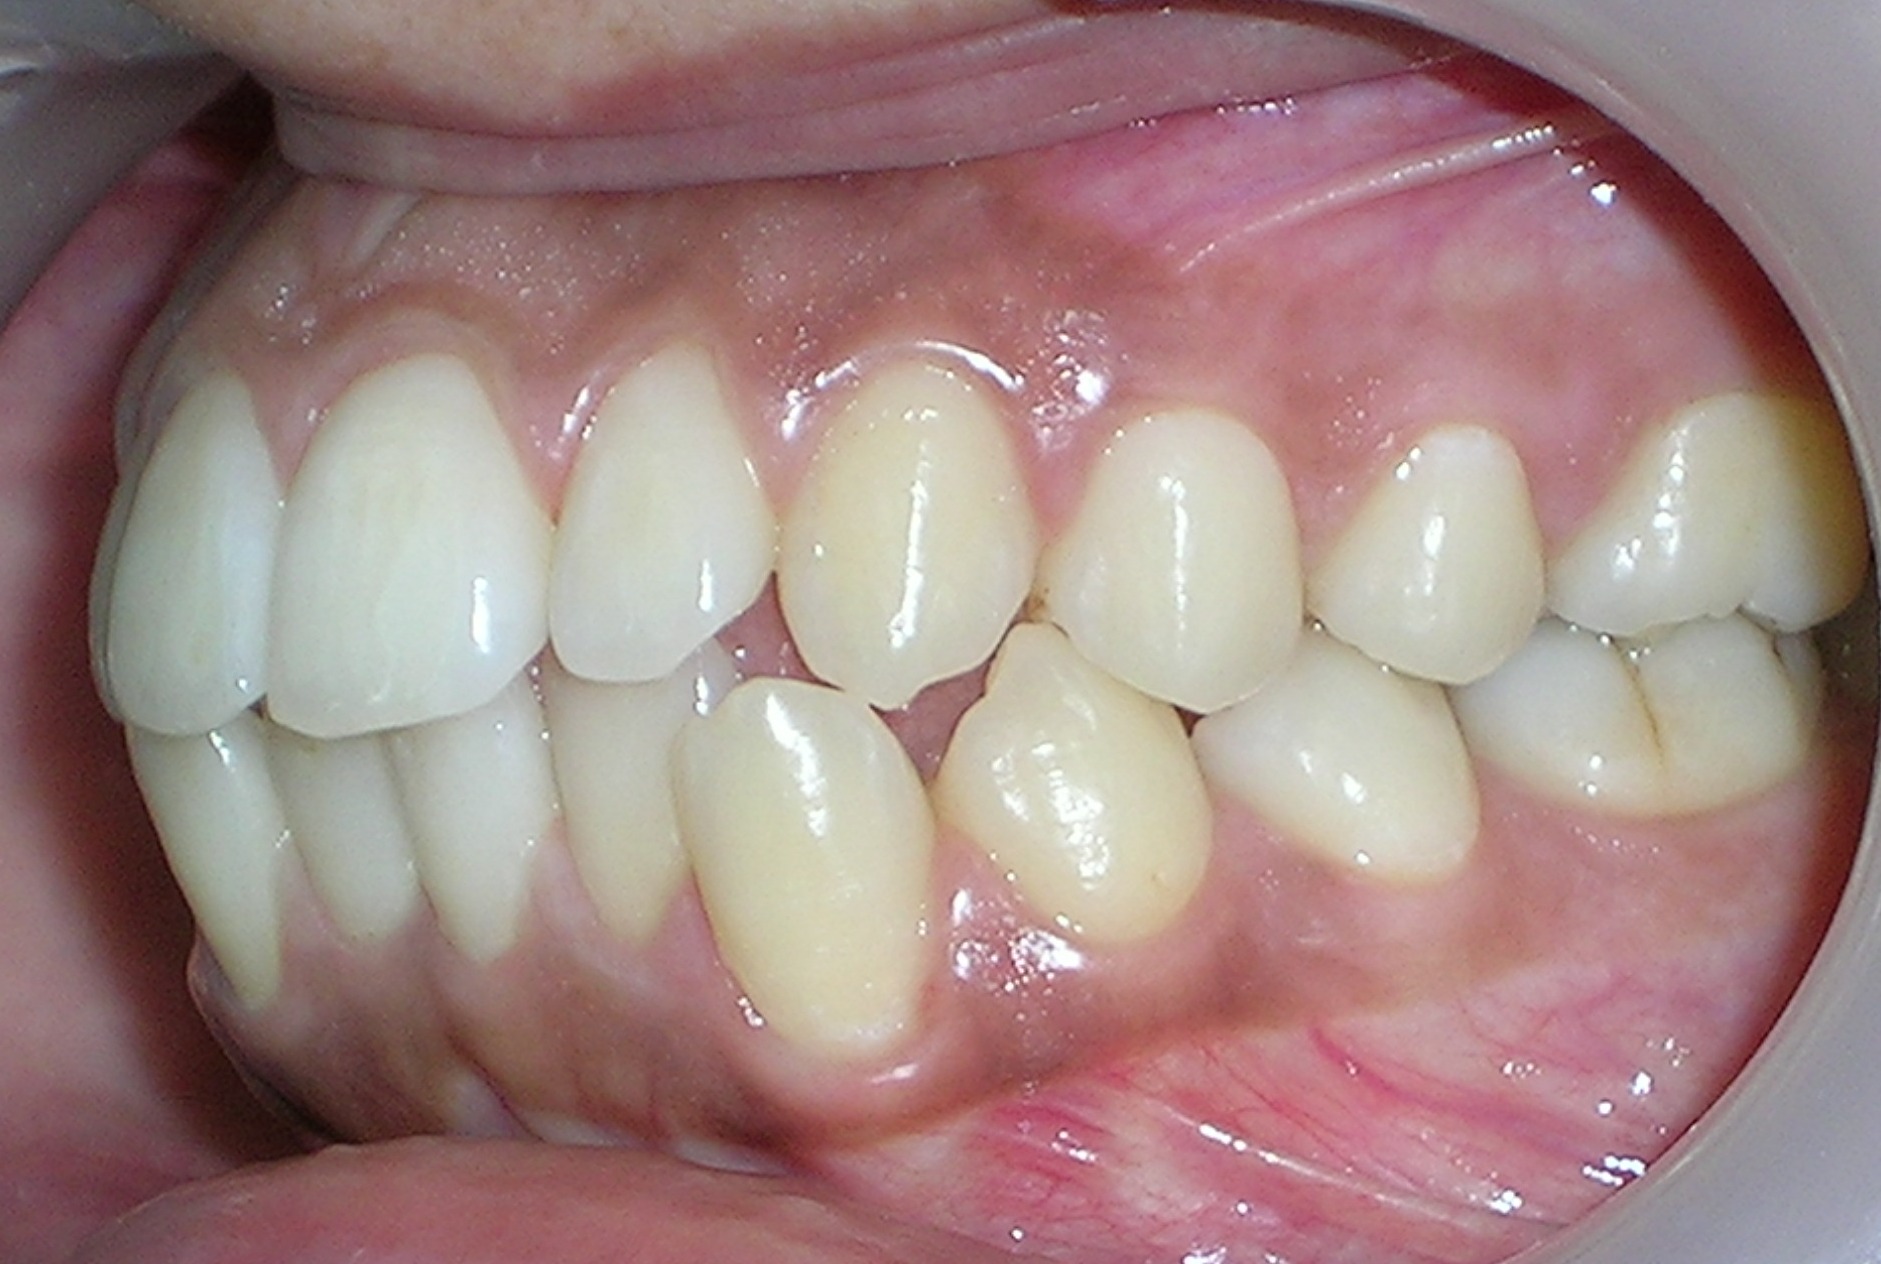

تعريف عام تقويم الأسنان هو فرع من طبِ الأسنان يَتخصّصُ في التشخيصِ ومنعِ ومعالجةِ الشذوذات والتغيرات في الأسنانِ والعظام الفكية الوجهية من حيث الموضع والحجم وعلاقة الأسنان والفكين ببعضها البعض. إنه يتعلق بتقويم الأسنان والفكين من أجل تحسين الابتسامة وصحة الفم. تعني كلمة "أورثو" أن الشيء سليم أو مستقيم في قوامه وتعني كلمة "أودونت" سنا. في العادة يوصي طبيب الأسنان بتركيب أجهزة تقويم الأسنان لتحسين المظهر الطبيعي لوجه وفم المريض. تَتطلّبُ ممارسةُ التقويم المعرفة المحترفة في وضع خطة العلاج وتطبيقِ الحاصرات السنية والتحكم بها لتحريك وجَلْب الأسنانِ والشفاهِ والفكين إلى الاصطفاف الصحيحِ والتوصّلُ إلى التوازنِ الوجهيِ. فمن خلال العلاج بتقويم الأسنان يتم معالجة المشاكل الناتجة عن الأسنان المتعوجة أو المتزاحمة وبروز الفك العلوي أو العضة المفتوحة وسوء وضعية الفك واضطرابات مفاصل الفك. بعد أخذ الأشعة والصور اللازمة يقوم طبيب التقويم بالعلاج اللازم وذلك بتثبيت أسلاك من المعدن على الأسنان أو يركب له جهاز متحرك ، ويتطلب ذلك العديد من الزيارات للطبيب على فترات متباعدة يحددها الطبيب المعالج حسب حالة كل مريض ويجب على المريض الاهتمام بتفريش أسنانه خلال فترة العلاج كي يتلافى ألإصابة بتسوس الأسنان أو ألتهاث اللثة نتيجة تراكم طبقة البلاك على أسنانه وأسلاك التقويم. التقويم يُمْكِنُ أَنْ يَرْفعَ ثقة الشخص بشكله ومظهره الشخصي عندما تصبح الأسنان والفكين والشفاه بوضعها الصحيح، لكن الابتسامةَ الجذّابةَ هي فقط إحدى فوائد التقويم الذي يؤدي أيضا لتَخفيف أَو مَنْع المشاكلِ الصحية بشكل عام، وهذا ما يعطي التقويم أهمية خاصة. فقط للحصول على ابتسامة رائعة و لكن صحّية أيضاً. الأسنان الموزعة باستقامة صحيحة في الفم تُحسّنُ إلى حد كبير الناحية الوظيفية في المضغ والبلع والكلام وتجعل التنظيف أسهل وأكثر فعالية وفائدة. الابتسامة الجميلة شيء رائع سواء عند امتلاكه أو رؤيته. الابتسامة الجذابة هي البداية فقط لكن تحسن الصحة الفموية والعامة تظل من الأهدافَ الم.همة في المعالجة التقويمة. أجهزة تقويم الأسنان الأجهزة الثابتة عبارة عن وحدات تقويمية صغيرة تثبت على كل سن، حيث يمرر بداخلها سلك معدني لتتم عملية تحريك الأسنان وهناك أنواع للحاصرات وهى: معدنية ستاليس ستيل ذات لون فظي. خزفية شفافة مشابهة للون الأسنان. ذهبية معدنية مطليه باللون الذهبي. هذه الأنواع جميعها تؤدى نفس الفعالية في العلاج والاختلاف الوحيد فيها هو لونها وشكلها الخارجي فالحاصرات المعدنية هى النوع السائد في التقويم بينما الخزفية نادرا ما تستخدم لأنها أغلى من المعدنية و.تحتاج إلى رعاية أكثر لسهولة كسرها وهى مرغوبة من النساء أكثر لأنها شفافة فلا يظهر من التقويم سوى السلك المعدني. اهمية تقويم الاسنان التنفس الصحيح استخدام الأطفال للمصاصة بالطريقة الخاطئة لمدة طويلة قد يؤدي الى ضيق الفك العلوي مما يسبب تنفس الطفل من فمه بدلاُ من انفه وهذه المشكلة سوف تصحح تلقائياً عند توسيع الفك العلوي باستخدام التقويم. الكلام بشكل جيد سوف يواجه ألإنسان صعوبة في النطق الجيد وذلك بسبب عدم انطباق الأسنان بالشكل الصحيح. وعدم القدرة على النطق الصحيح قد يؤثر على نفسية ألإنسان. الشكل الجميل إذا كانت وضعية الأسنان غير صحيحة فهذا سوف يؤثر على طريقة الكلام فستجد البعض يضع يده أمام فمه والآخر يقفل شفتيه ليخفي أسنانه وهذا بدورة سوف يجعل الكلمات غير واضحة واعوجاج وتزاحم أسنان الأطفال قد يؤثر على مستواهم الدراسي وذلك لخجلهم من أسنانهم فتراهم لا يشاركون ولا يتجاوبون مع مدرسيهم مما يجعل المدرسين يأخذون فكرة وصورة غير جيدة عنهم كعدم الاهتمام. الحالات التي تحتاج الى علاج التقويم التزاحم الشديد بين الأسنان الأمامية أو الخلفية – وجود فراغات كبيرة بين الأسنان الأمامية – وجود عضة أمامية مفتوحة – وجود عضة أمامية عميقة بحيث تغطي الأسنان الأمامية العلوية الأسنان الأمامية السفلية تغطية كاملة أو قريبة من الكاملة – وجود عضة أمامية معكوسة – عدم أو سؤ تطابق الأسنان الخلفية – بروز الأسنان الأمامية |